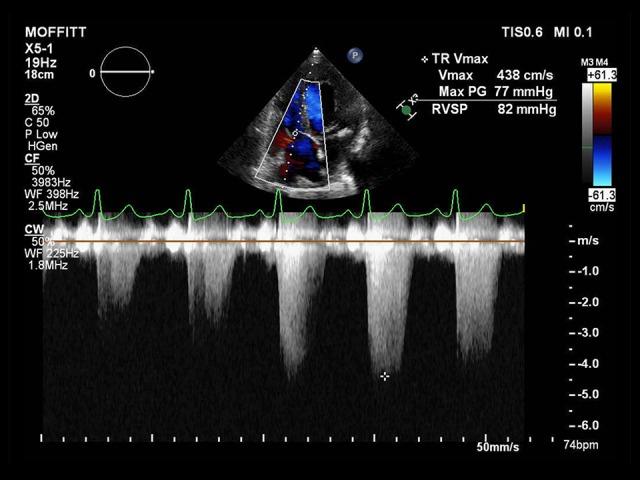

重度肺动脉高压患者的术中目标导向麻醉管理

Intraoperative Goal-Directed Anesthetic Management of the Patient with Severe Pulmonary Hypertension.

Department of Anesthesia, H. Lee Moffitt Cancer Center and Research Institute, Tampa, FL, USA.

BACKGROUND It is very challenging for anesthesiologists to manage patients with pulmonary hypertension undergoing general anesthesia for elective or emergent surgeries. CASE REPORT We present a patient with severe pulmonary hypertension going through a major robotic thoracic surgery. CONCLUSIONS A goal-directed anesthesia management algorithm based on serial stroke volume (SV) values obtained from FloTrac (Edwards Lifesciences, LLC.) minimally invasive arterial pressure sensor was utilized in an attempt to reduce the anesthetic and surgical risk associated with severe pulmonary hypertension.

摘要

背景

对于麻醉医生来说,管理患有肺动脉高压的患者接受择期或急诊手术的全身麻醉极具挑战性。

病例报告

我们介绍了一位患有严重肺动脉高压并接受大型机器人辅助胸外科手术的患者。

结论

采用了一种基于从爱德华生命科学有限责任公司的FloTrac微创动脉压传感器获得的连续每搏量(SV)值的目标导向麻醉管理算法,试图降低与严重肺动脉高压相关的麻醉和手术风险。